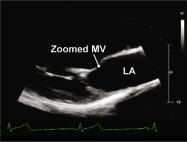

| 2.5. Mặt cắt trục dài cạnh ức qua đường ra thất phải |

||||||||

Cửa sổ siêu âm cạnh ức

Mặt cắt trục dài cạnh ức Ngửa và xoay đầu dò về phía đường ra thất phải/ |

Đường ra thất phải (RVOT) Van động mạch phổi (PV) Động mạch phổi (PA) |

|||||